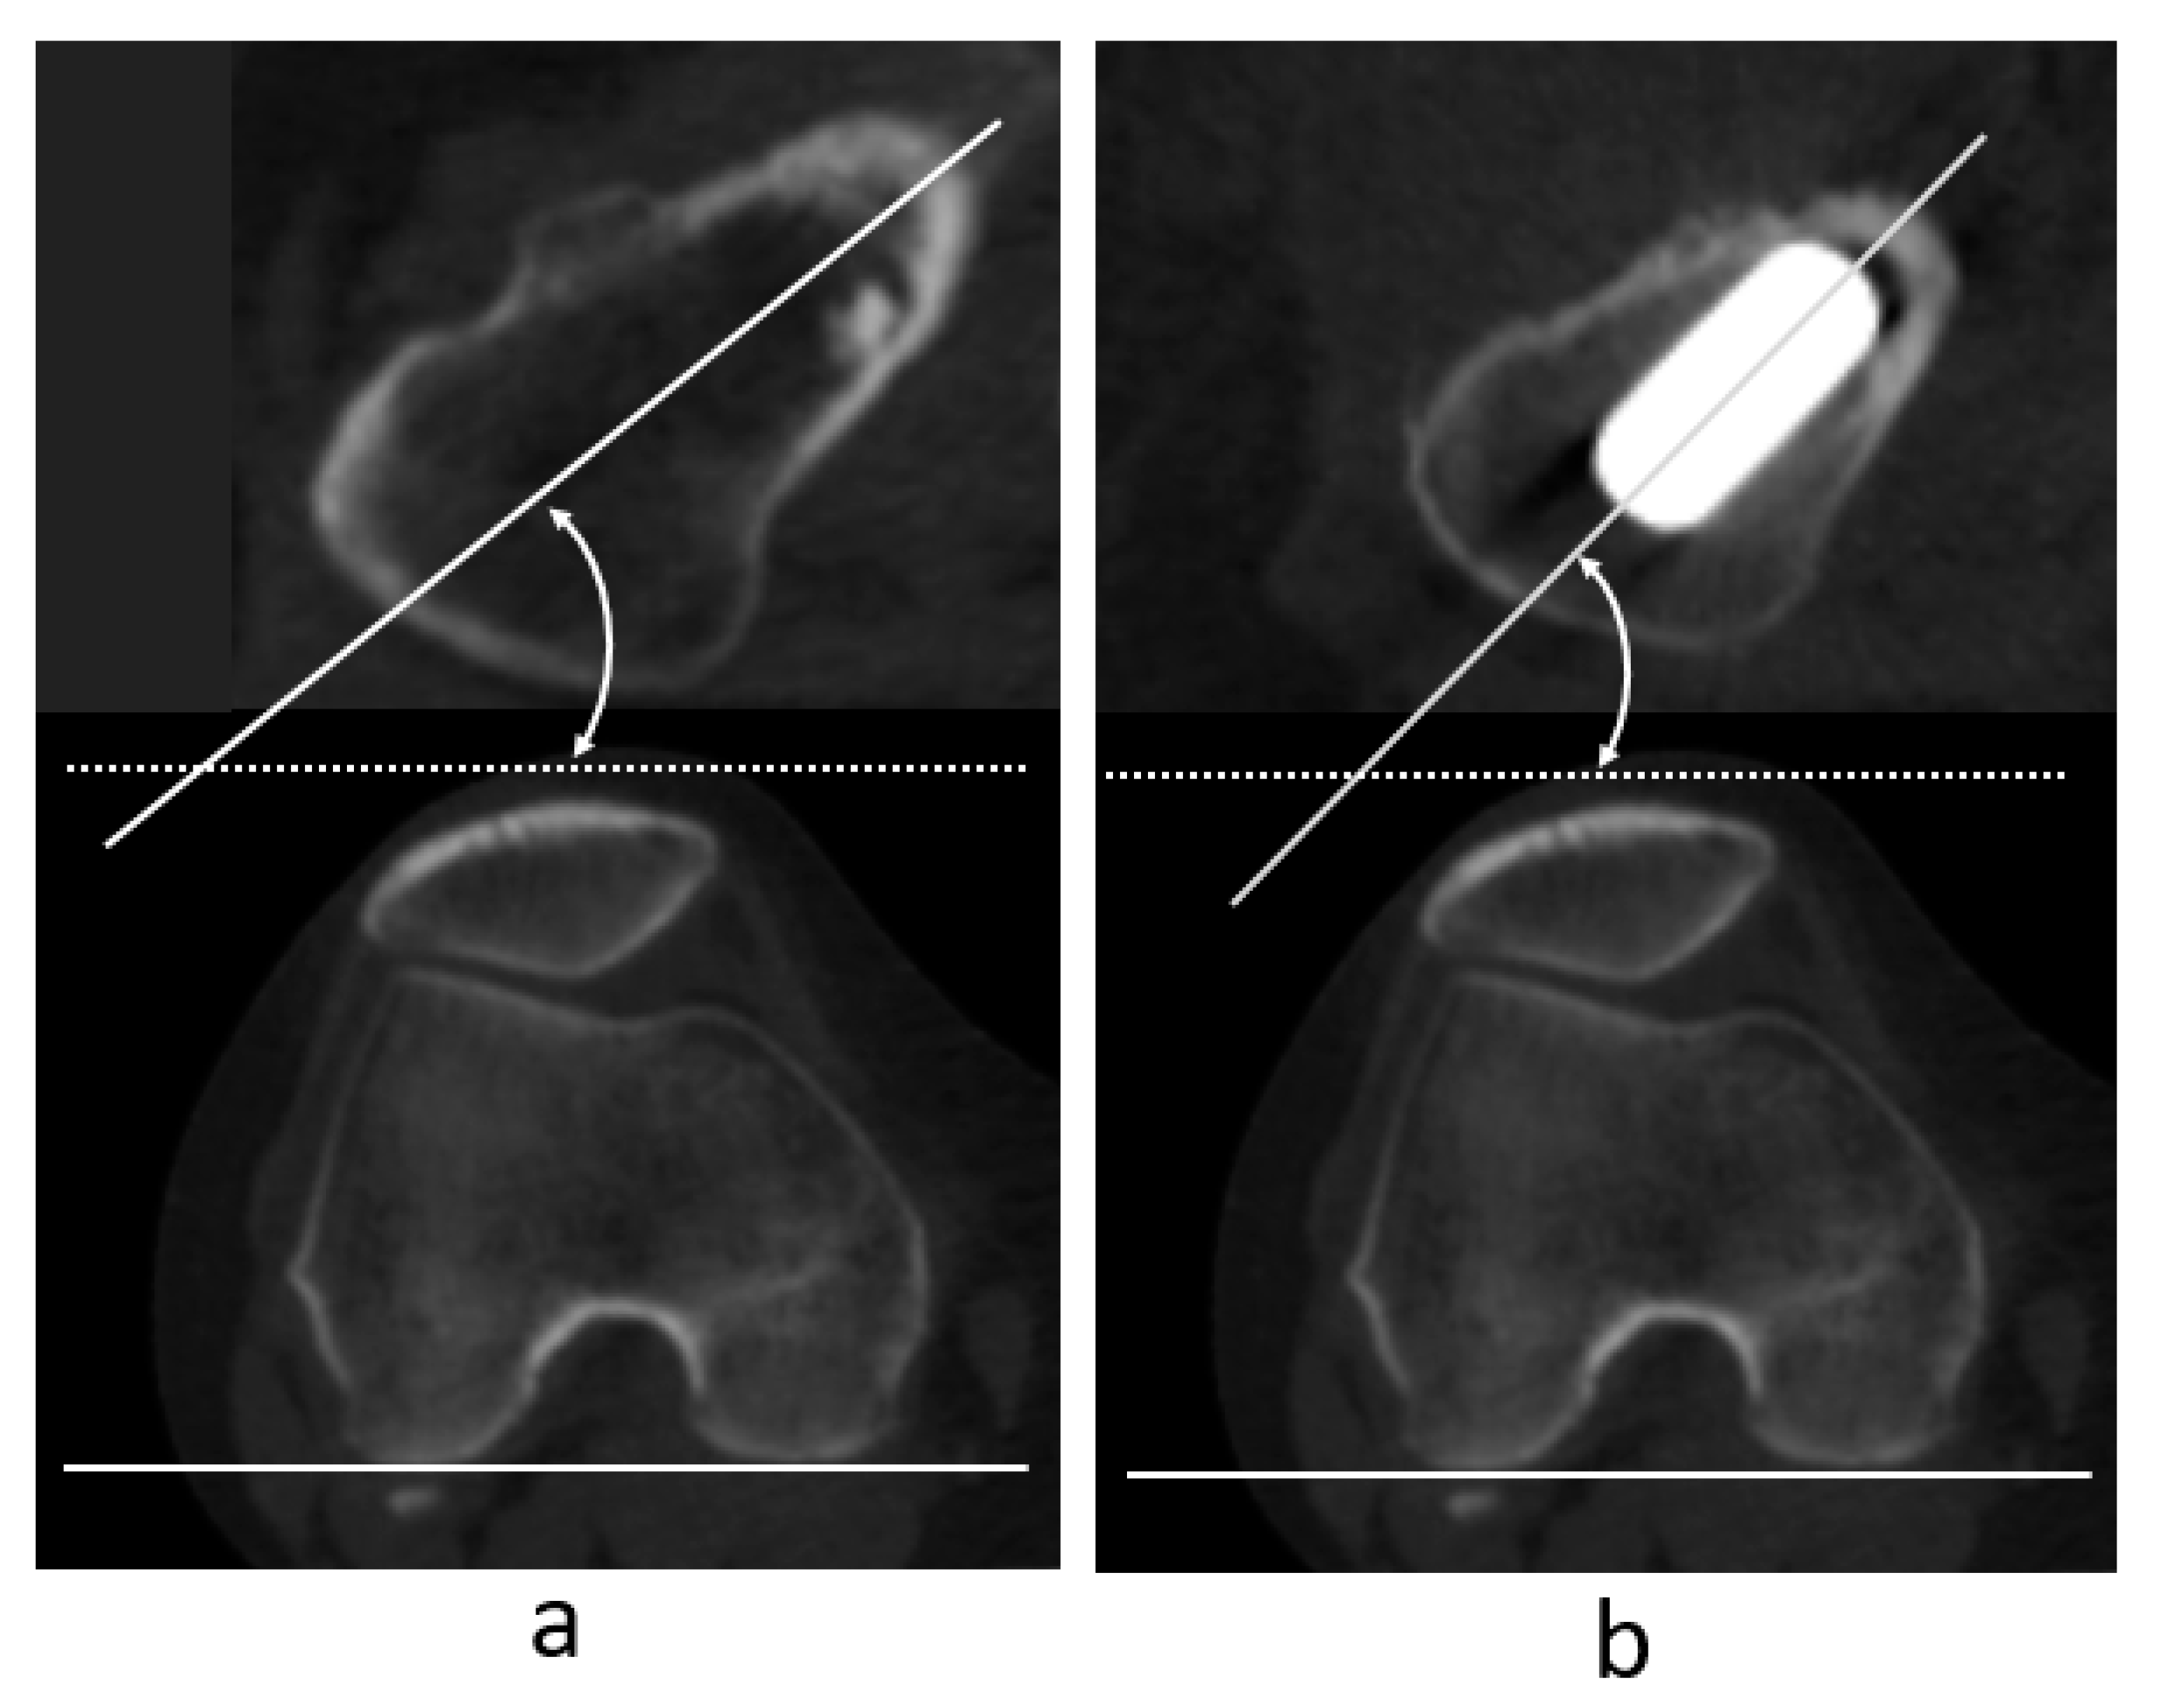

2.3. Measurement